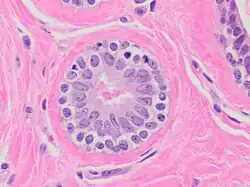

Acinus

De façon générale le terme acinus (du latin acinus, grain de raisin ; au pluriel acini ou acinus) désigne une cavité épithéliale arrondie bordée par des cellules sécrétrices qui débouche dans le canal excréteur d'une glande.

Acini séreux

- Cellule de forme pyramidale

- Lumière étroite

- noyau central arrondi

- Réticulum endoplasmique rugueux (RER) ou granuleux (REG) très développé, cytoplasme souvent basophile

- Présence de grain de sécrétion au pôle apical. Rejette son produit de sécrétion selon un mode mérocrine.

Exemple : acinus pancréatique